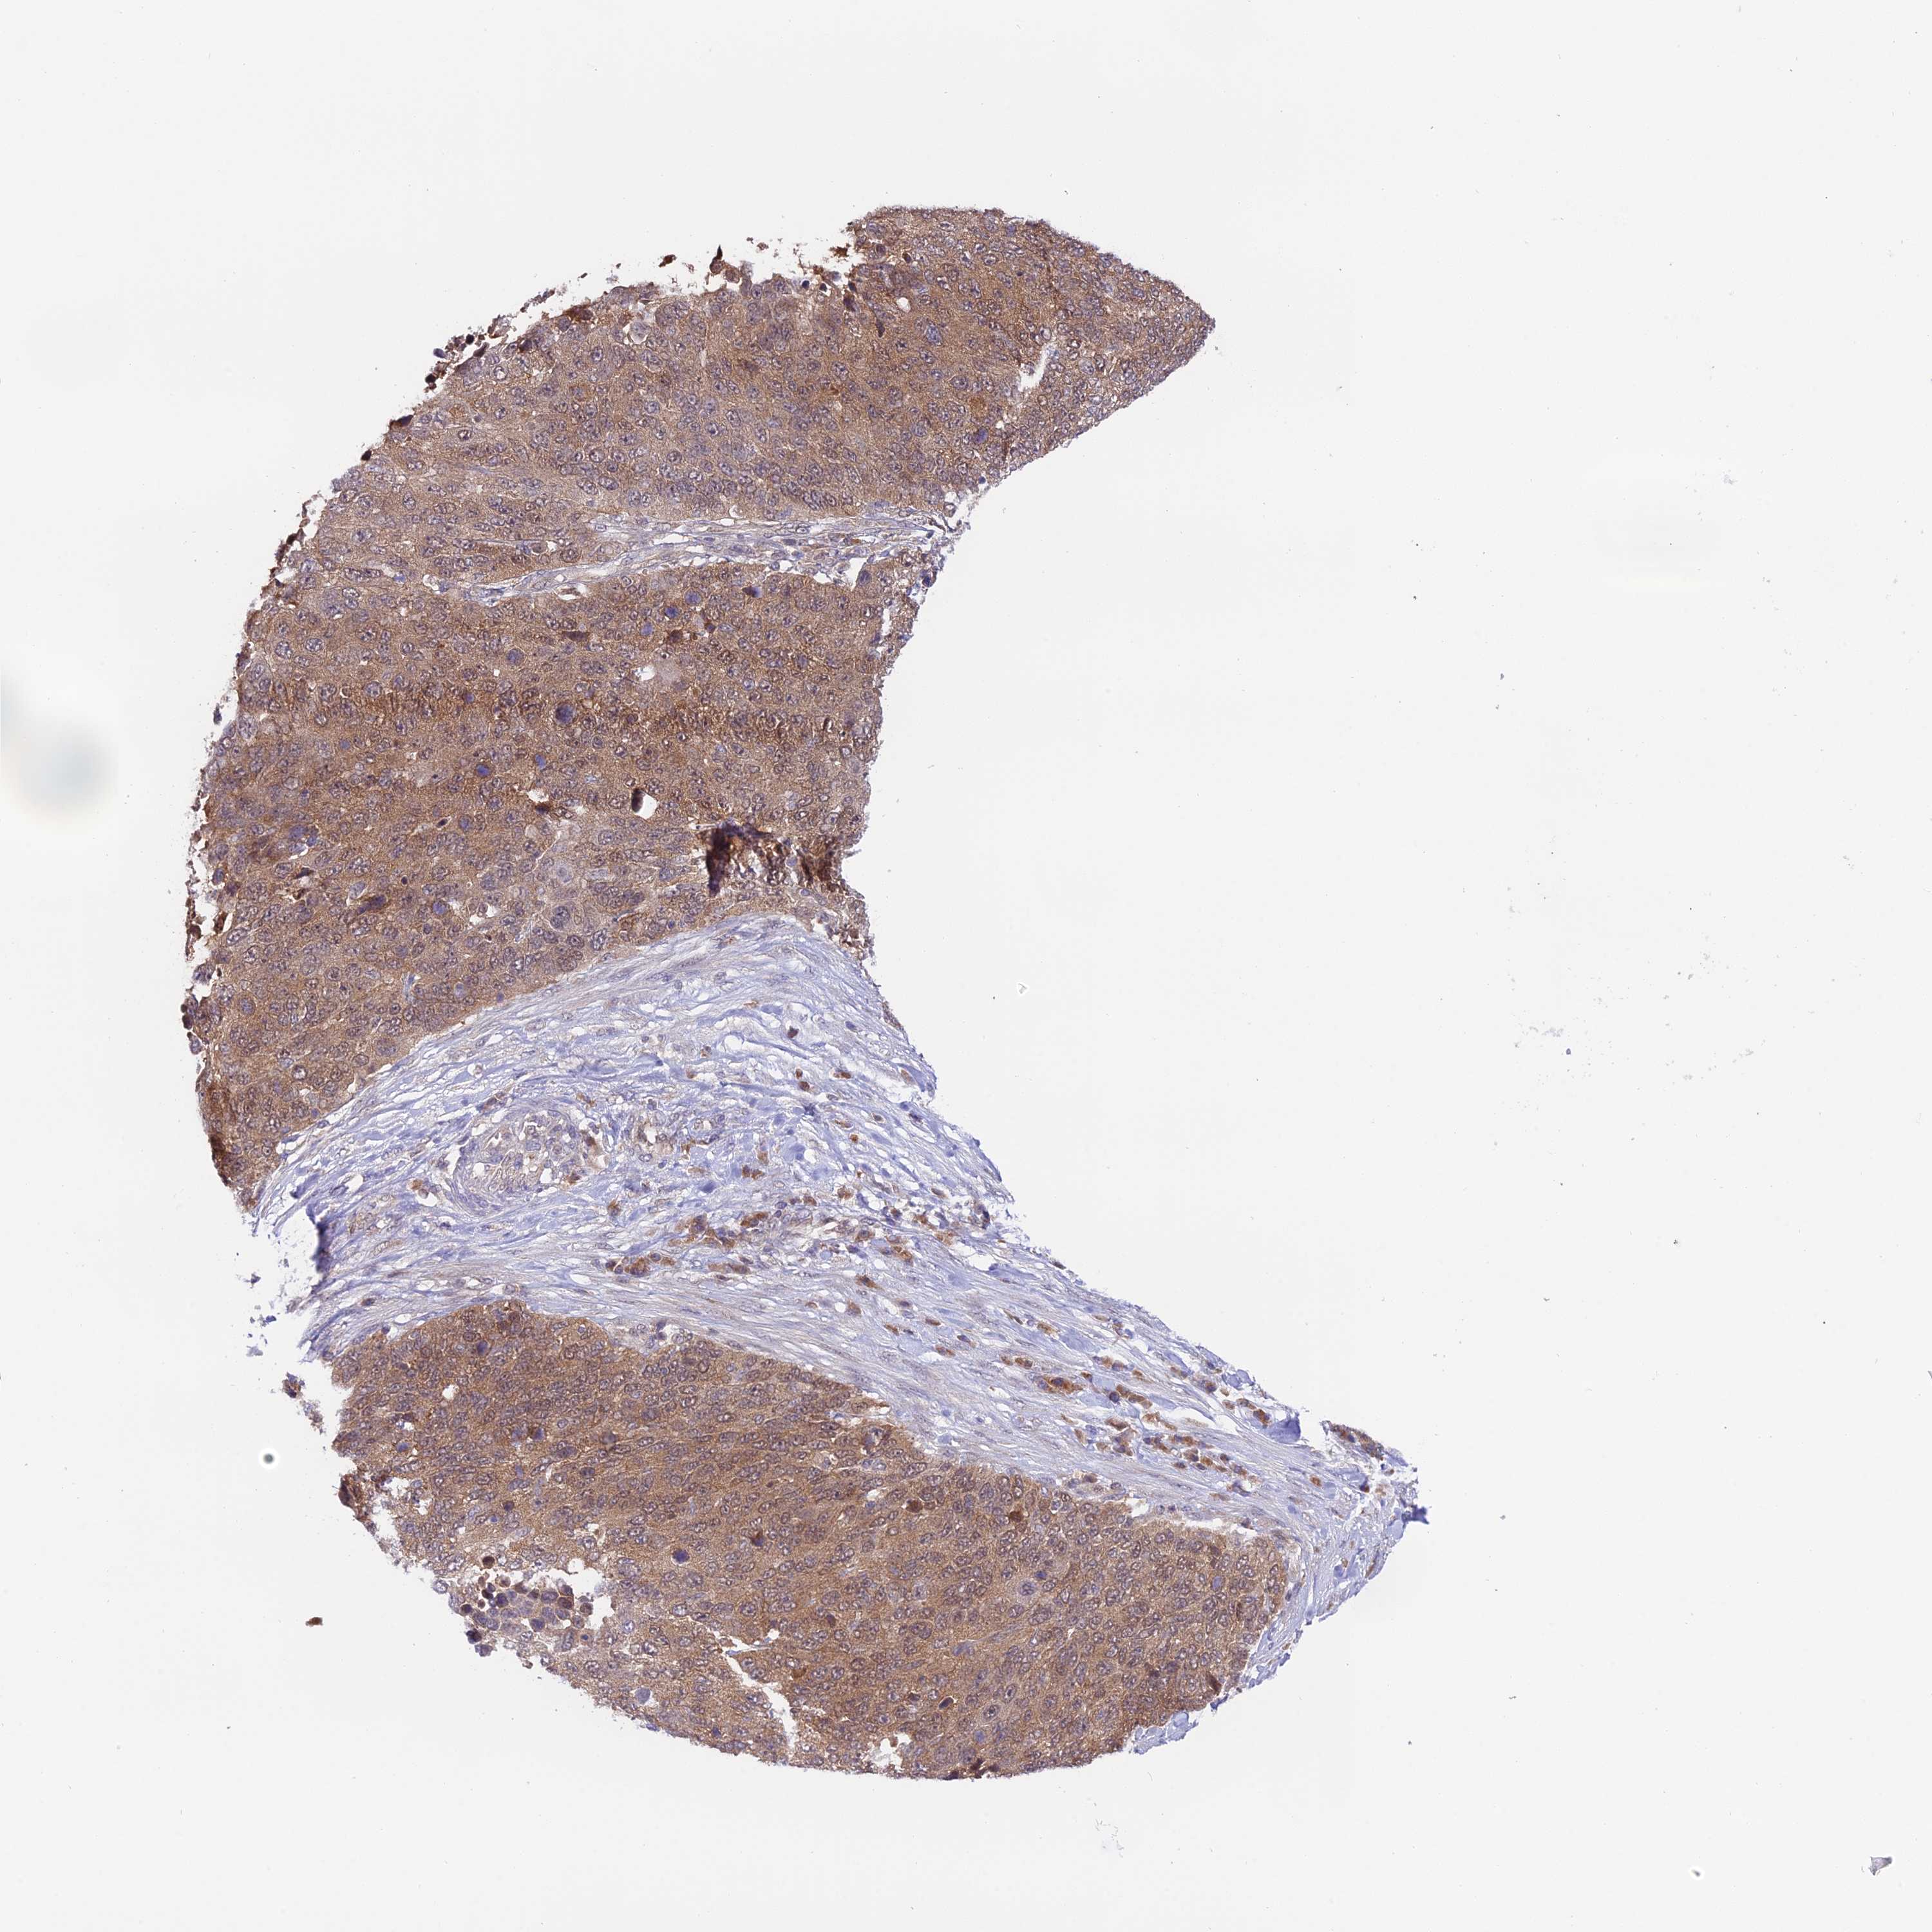

LUNG SQUAMOUS CELL CARCINOMA (TCGA) - Interactive survival scatter ploti

The Survival Scatter plot shows the clinical status (i.e. dead or alive) for all individuals in the patient cohort, based on the same data that underlies the corresponding Kaplan-Meier plots. Patients that are alive at last time for follow-up are shown in blue and patients who have died during the study are shown in red.

The x-axis shows the expression levels (FPKM) of the investigated gene in the tumor tissue at the time of diagnosis. The y-axis shows the follow-up time after diagnosis (years). Both axes are complimented with kernel density curves demonstrating the data density over the axes. The top density plot shows the expression levels (FPKM) distribution among dead (red) and alive patients (blue). The right density plot shows the data density of the survived years of dead patients with high and low expression levels respectively, stratified using the cutoff indicated by the vertical dashed line through the Survival Scatter plot. This cutoff is automatically defined based on the FPKM cutoff that minimizes the p-score. The cutoff can be changed by dragging the vertical line or by entering a cutoff value in the square labeled "Current cut-off".

Under the Survival Scatter plot the p-score landscape (black curve; left axis) is shown together with dead median separation (red curve; right axis). Dead median separation is the difference in median mRNA expression between patients who have died with high and low expression, respectively. It is calculated as follows: median FPKM expression of dead patients with high expression - median FPKM expression of dead patients with low expression. This is intended to aid the user in visually exploring custom cutoffs and the associated p-scores and dead median separation.

Individual patient data is displayed and can be filtered by clicking on one or more of the category buttons on the top of the page. Categories describing expression level and patient information include: high, low, alive, dead, female, male and tumor stages. The scale of the x-axis can be toggled between linear and log-scale by clicking on the "x log" button. Mouse-over function shows TCGA ID, patient information and mRNA expression (FPKM) for each patient.

& Survival analysisi

Kaplan-Meier plots summarize results from analysis of correlation between mRNA expression level and patient survival. Patients were divided based on level of expression into one of the two groups "low" (under cut off) or "high" (over cut off). X-axis shows time for survival (years) and y-axis shows the probability of survival, where 1.0 corresponds to 100 percent.

Survival analysis data not available.

TCGA RNA samplesi

RNA-seq data is reported as average FPKM (number Fragments Per Kilobase of exon per Million reads), generated by the The Cancer Genome Atlas (TCGA) .

Normal distribution across the dataset is visualized with box plots, shown as median and 25th and 75th percentiles. Points are displayed as outliers if they are above or below 1.5 times the interquartile range. FPKM values of the individual samples are presented next to the box plot.

Average pTPM 0.0

Number of samples 489